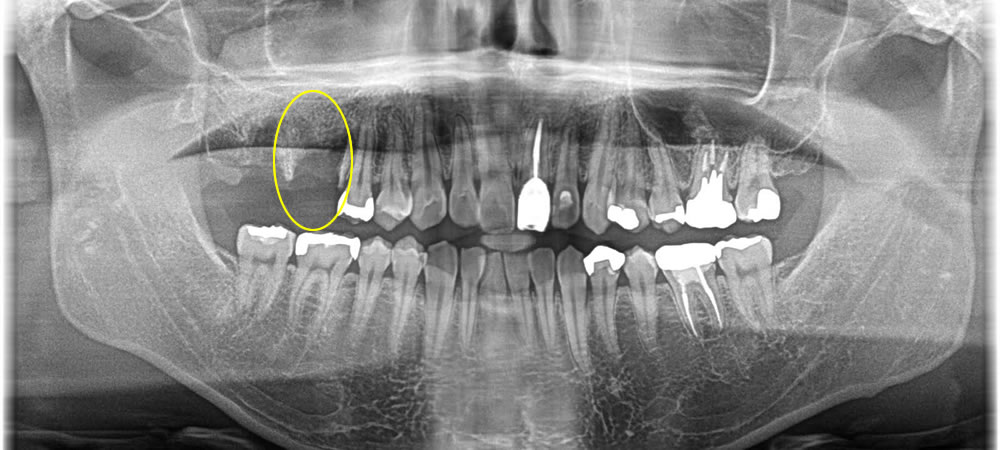

根尖性歯周炎の歯を抜歯即時埋入インプラントで治療した症例

年齢

50代

性別

男性

症例を見る